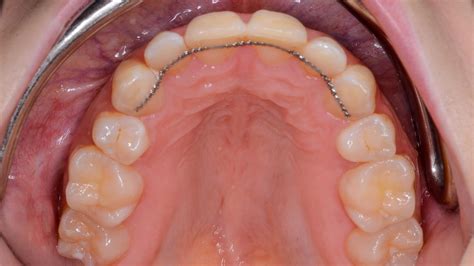

Los retenedores fijos consisten en un alambre delgado que se coloca en la parte posterior de los dientes. El funcionamiento de los retenedores fijos no es nada complicado. Se trata de que un alambre fijo actúe como una barrera para que los dientes vuelvan a desplazarse. Los retenedores dentales fijos son unos hilos de metal que se colocan en la cara interna de los dientes y se adaptan a su forma, de manera que quedan totalmente ocultos.

Se utiliza después del tratamiento de ortodoncia para que los dientes se adapten a su nueva posición de forma ordenada. Si no se utiliza este retenedor dental fijo hay una alta probabilidad de que los dientes vuelvan a su posición original y por tanto el tratamiento de ortodoncia no haya servido para nada.

- Adhesión del alambre en los dientes: El alambre fino se coloca detrás de los dientes incisivos, en la parte posterior y se fijan con un adhesivo especial.